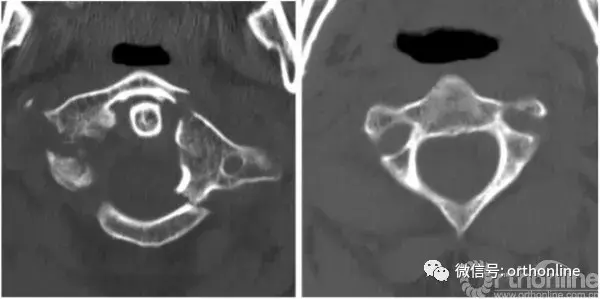

2014年5月,一名50岁男子因车祸入住我院。颈椎计算机断层扫描(CT)显示寰椎前弓及后弓多处骨折,侧块后1/3处分离(图1,左)。患者出现严重的颈部疼痛,当移动头部时疼痛剧烈,除此之外,无神经系统症状。同时合并有脑外伤、左侧额、颞部线性骨折以及头部软组织损伤,使我们在很长一段时间内无法使用Halo架固定。

最初,我们计划使用Harms技术进行C1-C2固定,用螺钉将寰椎碎裂的侧块融合。然而,病人的解剖特征使得这一方法不可行:其椎动脉位于C2椎体右侧,使右侧无法进行关节融合术。而C2右椎弓根、峡部、弧形部体积小,也使C1-C2的后路螺钉固定技术无法实施(图1,右侧)。由于这些限制,我们采用了前路经寰枢关节交叉螺钉固定技术(图2)和后路的Magerl技术[7]。

A 50-year-old man was admitted to our department in May 2014 after a car accident. Cervical spine computed tomography (CT) scans revealed multiple fractures in the anterior and posterior arcs of the atlas and abruption of the posterior third of its lateral mass (Fig.1,left). Clinical symptoms included severe cervical pain that increased dramatically when the patient moved his head; otherwise, he was neurologically intact. The concomitant traumatic brain injury, linear fracture of the left frontal and temporal bones, and soft tissue wound on the head prevented us from using the Halo device for an extended period of time. Initially, we planned to perform C1-C2 fixation using the Harms technique and fusion of the shattered lateral mass of the atlas with a screw. However, the patient’s anatomical characteristics prevented this. The location of the vertebral artery on the right side of the C2 vertebra made it impossible to perform transarticular fusion on that side. The small size of the C2 right pedicle, pars interarticularis, and arc also made it impossible to use the posterior screw fixation technique of C1–C2 on the right side (Fig.1,right). Due to these limitations, the combined anteroposterior atlantoaxial fixation technique with contralateral screw insertion (Fig.2) and Magerl trajectory[7]was performed.

Fig. 1 Case 1: pre-operative CT scan of the cervical spine. Left multisplintered fracture of the C1 vertebra. Right thinning pedicle, arc, and parsarticularis of the C2 vertebra as well as bilateral thinning of the anterior lip of the C2 lateral mass. CT computed tomography